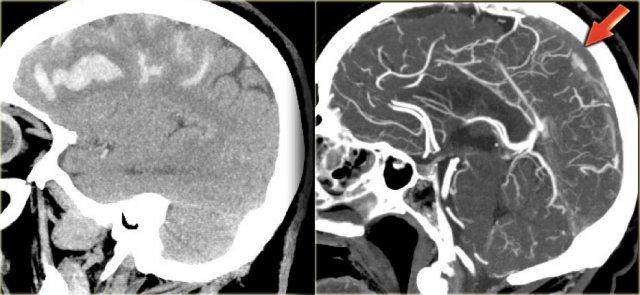

Hình ảnh bên trái là tái tạo CT mặt phẳng đứng dọc của một bệnh nhân có xuất huyết cạnh đường giữa hai bên do huyết khối xoang tĩnh mạch dọc trên.

Mũi tên đỏ trên hình CT có tiêm thuốc cản quang chỉ khuyết thuốc do huyết khối gây ra.

Nhồi máu tĩnh mạch (3) – Tĩnh mạch Labbe

Một dạng nhồi máu tĩnh mạch điển hình khác là do huyết khối tĩnh mạch Labbe.

Hình ảnh bên trái cho thấy giảm tỷ trọng ở chất trắng và ít rõ hơn ở chất xám của thùy thái dương trái.

Chẩn đoán phân biệt rộng bao gồm nhồi máu động mạch, nhiễm trùng, u não, v.v.

Lưu ý có một số đường tăng tỷ trọng trong vùng nhồi máu.

Đây là do xuất huyết.

Trong chẩn đoán phân biệt, cũng cần xem xét nhồi máu tĩnh mạch trong vùng phân bố của tĩnh mạch Labbe.

Tỷ trọng tăng nhẹ ở vùng xoang ngang trái (mũi tên) là chìa khóa để chẩn đoán.

Đây là dấu hiệu trực tiếp của huyết khối và bước tiếp theo là chụp CECT, xác nhận chẩn đoán (không hiển thị).